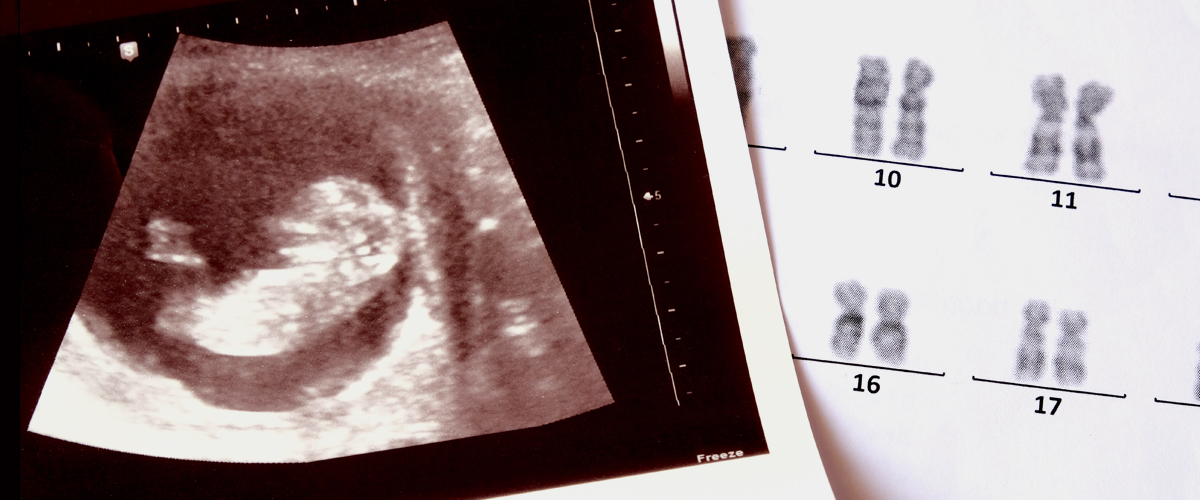

New Prenatal Test Can Reduce Time, Cost of Detecting Chromosomal Abnormalities